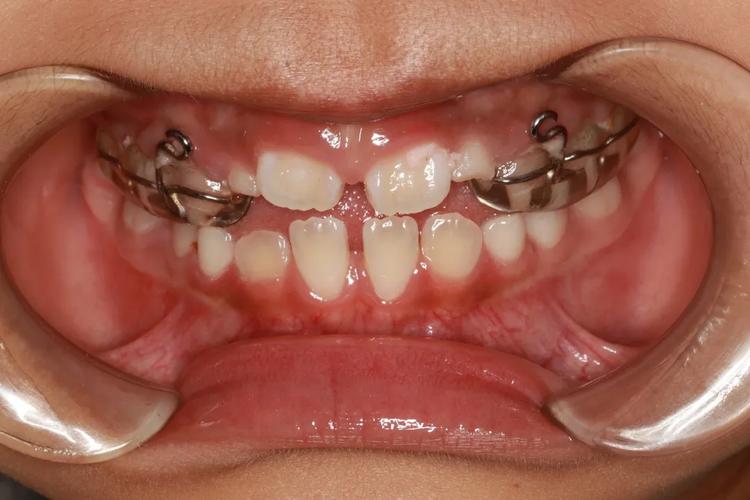

有的牙齿畸形是得认准8岁的这位“黄金窗口期”的,像“地包天”,也就是下牙把上牙给包住,要是不赶忙干预,会对上颌骨发育加以限制,致使面中部出现凹陷,从而形成“月牙脸”。另外还有严重的下颌后缩、偏颌,以及像长期吮指、吐舌等这般的口腔不良习惯,这些问题在8岁上下开展功能性矫治的话,能够借助孩子的生长发育潜力,能够通过事半功倍的方式来引导颌骨朝着正常的方向去生长。

众多家长觉得早期矫正仅仅是嘴上佩戴满齿的“钢牙套”,实则并非如此。8岁这个阶段的干预方式主要是“阻断性”以及“引导性”的。极为常见的是活动矫治器,孩子于晚上佩戴或每日戴足规定时长就行;另外还有针对“地包天”的前方牵引面具,或者用于纠正不良习惯的舌栅、唇挡之类工具。此阶段的目的并非将牙齿排列得毫无瑕疵,而是消除颌骨发育的阻碍,为后续恒牙萌出营造空间,好多情形在做完一期之后,甚至无需再做二期矫正。